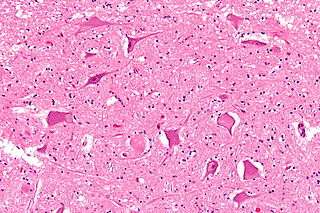

Chromatolysis is the dissolution of the Nissl bodies in the cell body of a neuron. It is an induced response of the cell usually triggered by axotomy, ischemia, toxicity to the cell, cell exhaustion, virus infections, and hibernation in lower vertebrates. Neuronal recovery through regeneration can occur after chromatolysis, but most often it is a precursor of apoptosis. The event of chromatolysis is also characterized by a prominent migration of the nucleus towards the periphery of the cell and an increase in the size of the nucleolus, nucleus, and cell body.[1] The term "chromatolysis" was initially used in the 1940s to describe the observed form of cell death characterized by the gradual disintegration of nuclear components; a process which is now called apoptosis.[2] Chromatolysis is still used as a term to distinguish the particular apoptotic process in the neuronal cells, where Nissl substance disintegrates.

Central chromatolysis is the most common form of chromatolysis and is characterized by the loss or dispersion of the Nissl bodies starting near the nucleus at the center of the neuron, and then extending peripherally towards the plasma membrane. Also characteristic of central chromatolysis is the displacement of the nucleus towards the periphery of the perikaryon.[3][4][5] Other cellular changes are observed during the process of the central chromatolysis. The process of Nissl dissolution is less apparent toward periphery of the cell body of the neuron, where normal-looking Nissl bodies may be present.[1] Hyperplasia of neurofilaments is frequently observed, however the extent varies. The number of autophagic vacuoles and lysosomal structures often increase during central chromatolysis. Changes can also occur in other organelles such as the Golgi apparatus and neurotubules. However, the exact significance of these changes is currently unknown. In neurons receiving axonal transection, central chromatolysis is observed in the area between the nucleus and the axon hillock following.......[6]

Peripheral chromatolysis is much less common, but has been reported to occur after axotomy and ischemia in certain species. Peripheral chromatolysis is essentially the reverse of central chromatolysis, in which the disintegration of Nissl bodies is initiated at the periphery of the neuron and extends inwards towards the nucleus of the cell. Peripheral chromatolysis has been observed to occur in lithium-induced chromatolysis and it could be useful in investigating and countering the hypothesis that waves of enzymatic activity always progress from the perinuclear area, or the area situated around the nucleus, to the peripheral of the cell.[7]